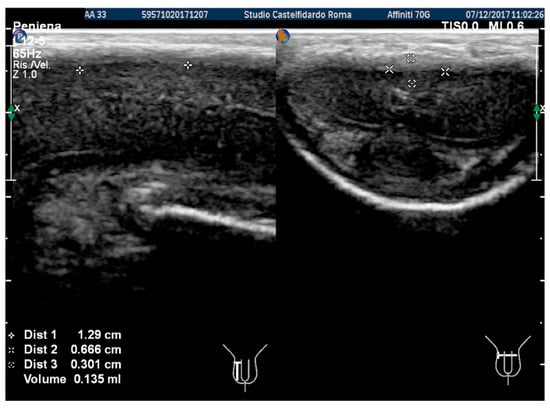

At the end of the first treatment cycle, at follow-up, the patient filled out the IIEF questionnaire, and the score was 26. We then observed a left penile curvature with a decreased angle (to 25 degrees). The pain in the penis had gone. The penile ultrasound showed the following dimensions: 6.33 × 5.58 × 2.66 mm (49 mm3 = volume) (Figure 2).

Figure 2. Ultrasonography of the penis after the 1st therapy cycle (longitudinal and axial views).